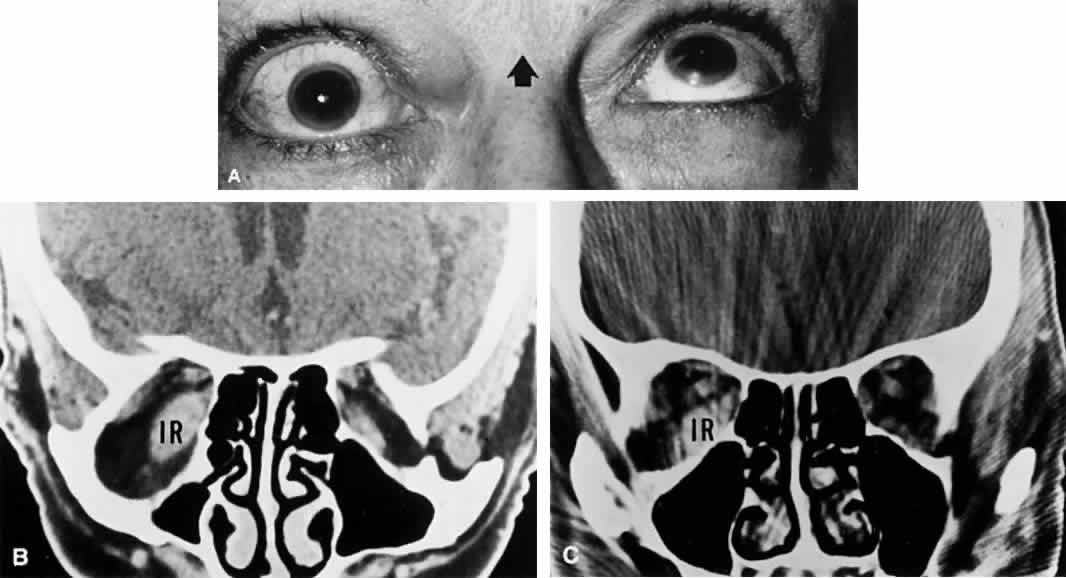

Clinically, patients with ischemic oculomotor palsy present with acute pain in and about the involved eye. The pain may precede actual ophthalmoplegia and can be so severe as to suggest a bleeding aneurysm (but without neck stiffness, photophobia, obtundation, etc.), or it may accompany the onset of ptosis or diplopia as a mild brow pain or headache. The pupil is almost always spared, in contradistinction to posterior communicating artery aneurysm (see above). Iridoplegia, when present, is moderate. Ophthalmoplegia may be partial, with some muscles spared entirely (Fig. 14). Recovery is predictable, occurring after several weeks and usually before 4 months.

Fig. 14. Ischemic (diabetic) right oculomotor ophthalmoplegia of mild degree. A. Note failure of adduction on left gaze and unusual lack of ptosis. B. Pupil is spared, with intact light reaction. C. Superior rectus weakness. D. Inferior rectus weakness. Mild pain accompanied onset of diplopia, with complete resolution in 3 weeks. This was the second episode in a 62-year-old patient with known diabetes.